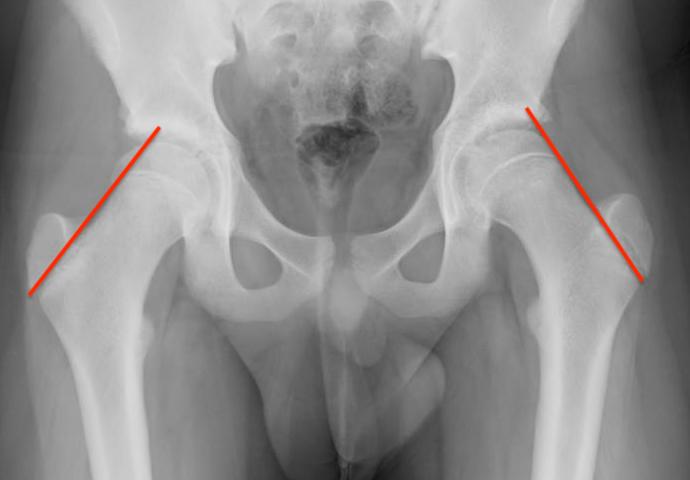

AP Xray

Widened eipiphysis

Klein's Line

- line along superior neck should transect part of epiphysis

Mild slip with failure of Klein's line to transect epiphysis